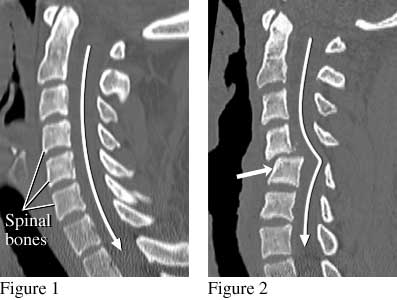

CT scan of the cervical spine (neck) showing a normal and a dislocated spine

The side view of the spine (figure 1) shows the normal position of the spinal bones. The spinal cord (not visible in this image) follows the path of the long white arrow. Figure 2 shows shifted spinal bones (short thick arrow) from a fracture that damaged the spinal cord. This person was paralyzed after being ejected during an automobile crash while not wearing a seat belt.